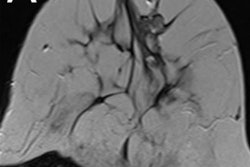

Breast MRI with a shorter screening protocol can still help detect cancer recurrence for women with a personal history of breast cancer, according to a study published on March 12 in PLOS One. Abbreviated MRI with an 11-minute protocol identified almost a dozen cancers missed by alternative screening modalities.

Breast cancer treatment can result in increased breast density, scarring, and fibrosis, which in turn can lead to architectural distortion on mammograms. The new research shows that, even with a shorter examination time, MRI may be able to find some malignancies more difficult to identify through mammography or ultrasound.

Abbreviated MRI has a shorter image acquisition time than traditional MRI, with similar diagnostic accuracy. It's also cheaper than conventional MRI, making it more competitive with ultrasound and mammography for breast cancer screening.